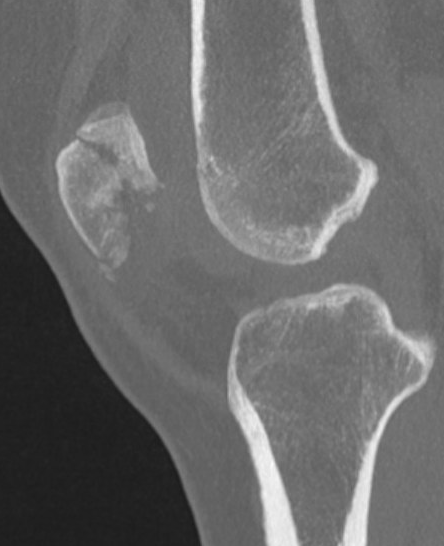

CT

Osteochondral fracture of the lateral femoral condyle

Large osteochondral fracture medial facet patella

Large osteochondral fracture lateral femoral condyle